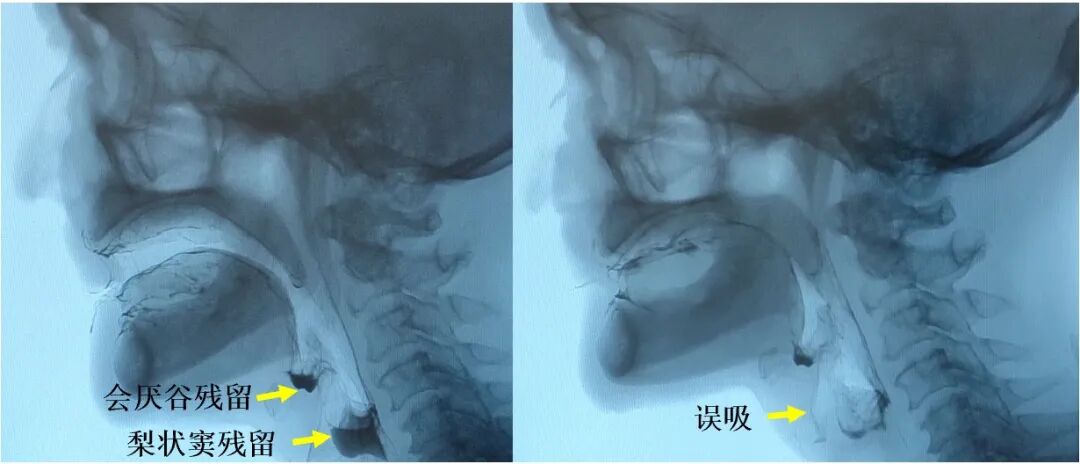

咽缩肌的病理组织改变的减轻最终在功能效应层面表现为咽缩肌功能的显著改善。造影检查显示,对比标准放疗组,内侧组咽后区豁免放疗组中出现会厌谷残留(74% 对比 100%;P<0.001)、梨状窦残留(48% 对比 73%;P=0.01)、咽后壁残留(11% 对比 27%;P=0.01)、咽通过时间>1.0秒(2% 对比 11%;P=0.03)及误吸(12% 对比 29%;P=0.03)等咽期受损表现的频率均更低。

图4:造影检查所示会厌谷残留、梨状窦残留及误吸